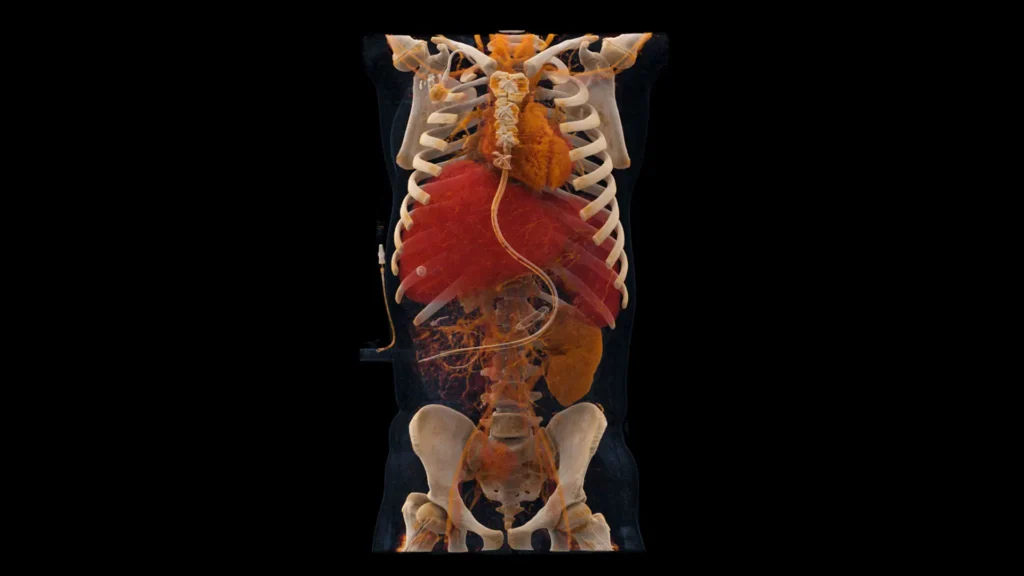

All’Ospedale Pederzoli di Peschiera del Garda è stata installata, per la prima volta in Italia, la NAEOTOM Alpha.Prime che rappresenta la più avanzata tecnologia oggi disponibile nel campo della diagnostica per immagini mediante TC.

L’apparechiatura utilizza la tecnologia a conteggio di fotoni (Photon Counting CT) che associata a programmi di intelligenza artificiale, ridefinisce l’eccellenza diagnostica in termini di accuratezza, riduzione della dose di esposizione e quantità di mezzo di contrasto somministrato.

La NAEOTOM Alpha Prime permette di calibrare lo studio sulla scorta del quesito clinico consentendo un processo diagnostico più efficace e tempestivo, migliorando l’accuratezza clinica e supportando lo Specialista nella scelta del percorso terapeutico più appropriato.

- Immagini a risoluzione ultra-definita, che consentono una visualizzazione dettagliata delle strutture anatomiche dagli organi ed apparati più complessi a quelle di dimensioni estremamente ridotte come la catena ossiculare dell’orecchio medio;

- Riduzione significativa della dose di radiazioni e della quantità di contrasto somministrata, a beneficio della sicurezza del paziente;

- Riduzione della durata delle indagini che garantisce esami più rapidi e confortevoli, anche per i pazienti più fragili.